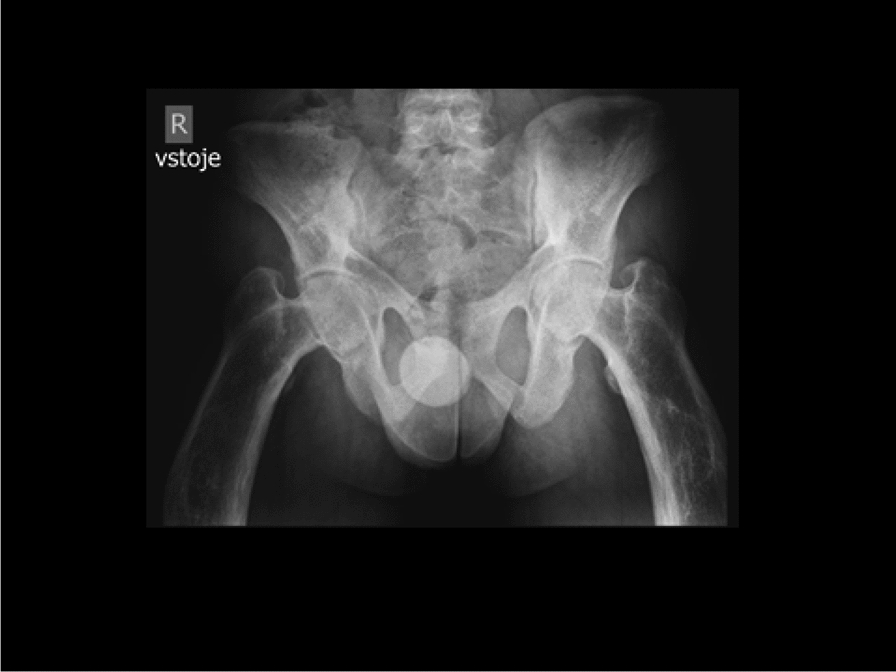

Methods and results: We report the first case of JPD diagnosed in the Czech Republic, who presented with a mild phenotype of this disease. The first bone fractures, appeared at 3 years of age. Other clinical manifestations included typical skeletal deformities, macrocephaly, arched chest, lower extremity valgosity, lateral bowing of the thighs, and anterior bowing of the shins. Minor mixed hearing impairment, angioid stripes of the choroidea, and temporary immunodeficiency were present among extra-skeletal findings. Sanger sequencing was performed on both the patient and the parents to test for the presence of TNFRSF11B sequence variants. Molecular genetic analysis showed unique compound heterozygous sequence variants in TNFRSF11B: a paternally inherited variant c.30 + 5G > A, p.(?) and a maternally inherited variant c.329G > T, p.(Gly110Val). Both of the variants were analyzed by several in silico predictive tools indicating, for their strongly supported pathogenicity according to American College of Medical Genetics and Genomics standards. Furthermore, we present diagnostic findings, their treatment, and follow-up care.